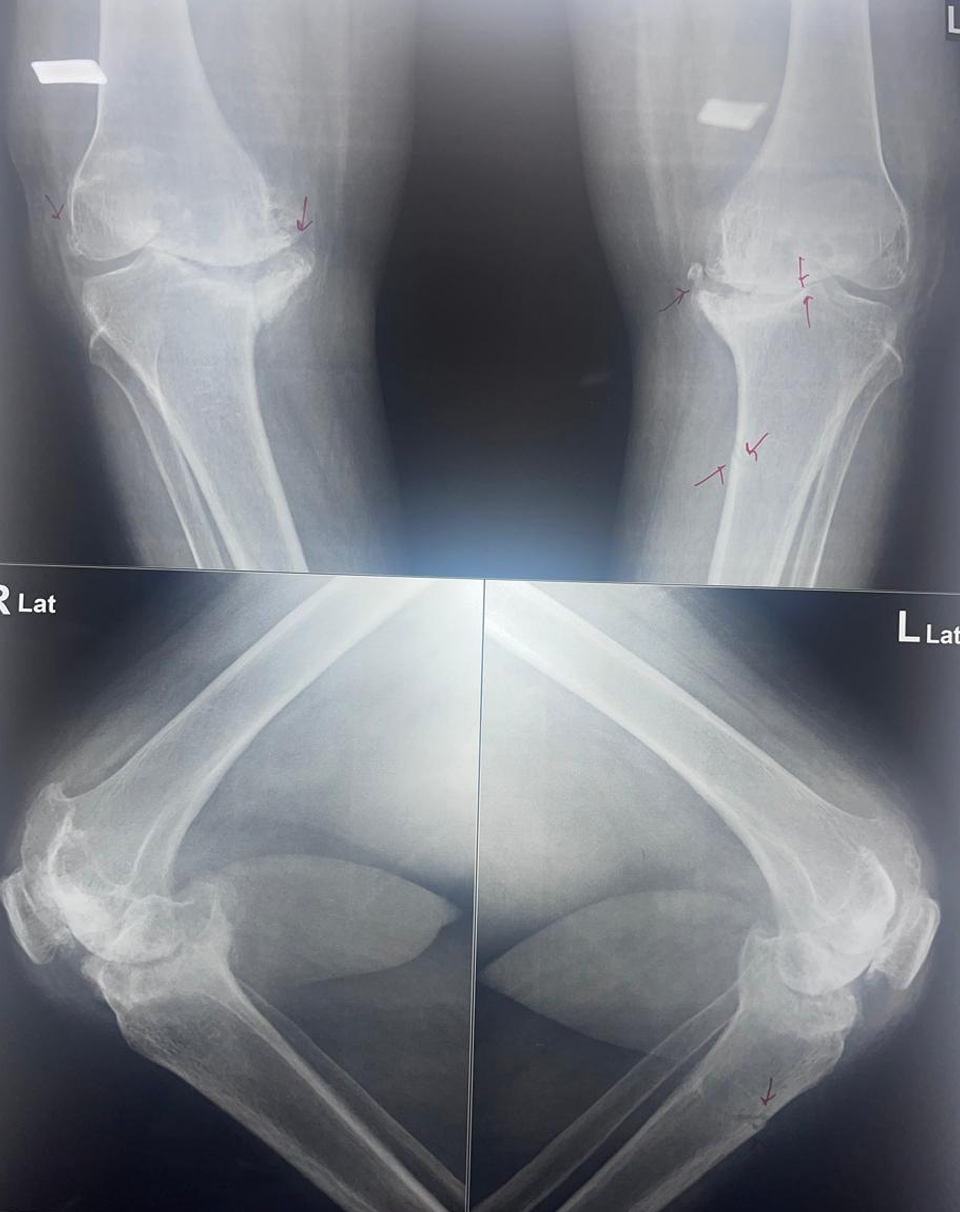

Talk on painfull knee in SL Raheja Hospital